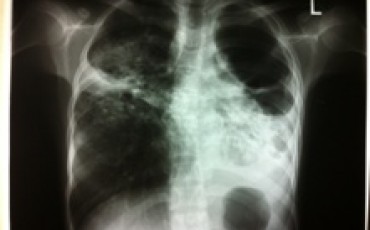

Image: Measurement of nitric oxide in exhaled breath in a person with TB.